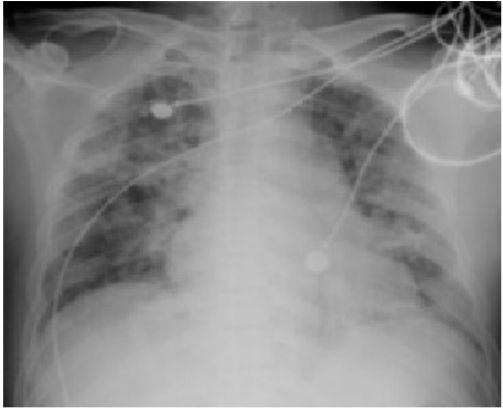

12. 某45歲男性已有高血壓5年,最近檢查有血尿RBC 10-20/HPF、Cre 1.2 mg/dL、超音波檢查發現兩側腎臟長徑超過15公分(如圖)及各有囊腫數目超過十個;家族史為父親自60歲開始血液透析,不曾顱內出血,父親的腎臟超音波亦有雷同的發現。 請問關於其腎臟疾病之敘述,下列何者為正確?(1)每年定期追蹤腎功能,即為預估日後是否需要透析治療之最敏感方法;(2)若其太太懷孕可做產前篩檢,其子女遺傳此腎臟疾病的機會為50%;(3) 以影像學檢查估算其腎臟體積,若超過600立方公分,其腎功能極可能持續逐年惡化;(4) 雖無症狀,應每年安排腦部血管Magnetic resonance angiography的檢查;(5)宜建議停止服用含女性荷爾蒙之避孕藥。 (A) (1)+(2)+(3) (B) (1)+(3)+(4) (C) (2)+(4) (D) (4)+(5) (E) (2)+(3)+(5)